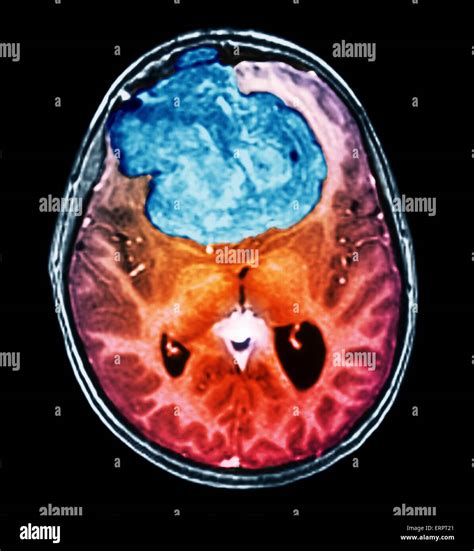

• Imaging Tests: Imaging tests such as X-rays, CT scans, MRI scans, and PET scans can help visualize the tumor or tumour and determine its size, location, and extent.

• Biopsy: A biopsy involves removing a small sample of tissue from the tumor or tumour for examination under a microscope. This can help determine whether the tumor or tumour is benign or malignant.